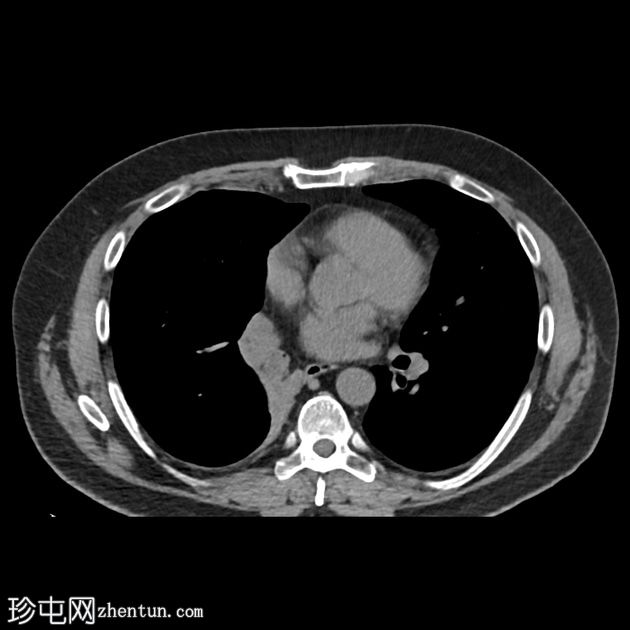

在一次时机不佳的动脉期CT扫描中,我们发现右下支气管内有一个低强化肿块。

左肾内偶然发现一个较大的、中心坏死的肿块。

右侧肾上腺可见几个小的低密度结节。

另需注意环状伪影(CT机随后不久更换)。